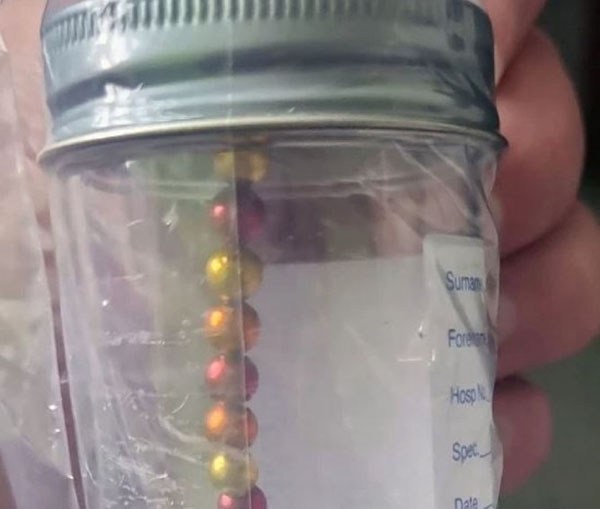

ஆம், Beccaவின் வயிற்றுக்குள் உருண்டையான பொருட்கள் சில சங்கிலிபோல் இணைந்திருந்ததைக் கண்ட மருத்துவர்கள், அவை உலோகத்தாலான பொருட்கள் என தெரியவந்ததையடுத்து அவளுக்கு அ.று.வை சி.கி.ச்.சை செ.ய்.ய மு.டி.வு.செ.ய்.தனர்.

அதற்காக Beccaவின் குடல் த.ற்.கா.லி.க.மாக அ.க.ற்.ற.ப்பட்டது. அந்த குடலை ப.ரி.சோ.தி.த்த ம.ரு.த்.து.வர்கள், குழந்தை காந்த உருண்டைகளை விழுங்கியிருப்பதைக் கண்டுபிடித்தனர்.

பல வண்ணங்களில் இருந்த அந்த காந்த உருண்டைகளை குழந்தை மிட்டாய் என்று எண்ணி விழுங்கியிருக்கிறாள். இரண்டரை மணி நேர அ.று.வை சி.கி.சை.க்குப்பி.ன் காந்த உருண்டைகளை அ.க.ற்றி குடலை இணைத்துள்ளனர் மருத்துவர்கள்.